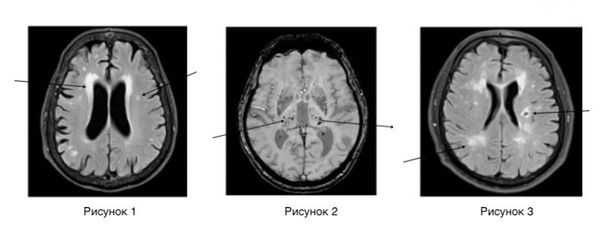

Нейровизуализационные методы: КТ, МРТ головного мозга, МР-ангиография (артерии и вены головного мозга ), при необходимости рентгеноконтрастная церебральная ангиография. Нейровизуализация позволяет исключить другие заболевания (опухоль, гидроцефалию) и подтвердить сосудистый характер нарушений. Предпочтительнее МРТ головного мозга, на которой выявляются характерные для хронической ишемии мозга изменения:

- лейкоареоз — изменение белого вещества вокруг желудочков головного мозга (на рисунке 1, белое свечение вокруг желудочков);

- лекоэнцефалопатия — поражение белого вещества головного мозга (на рисунке 1 и 3, светлые участки в подкорковом веществе);

- малые инфаркты, ишемические инсульты (рисунок 3);

- множественные микрокровоизлияния (рисунок 2 — темные участки);

- атрофия коры головного мозга.